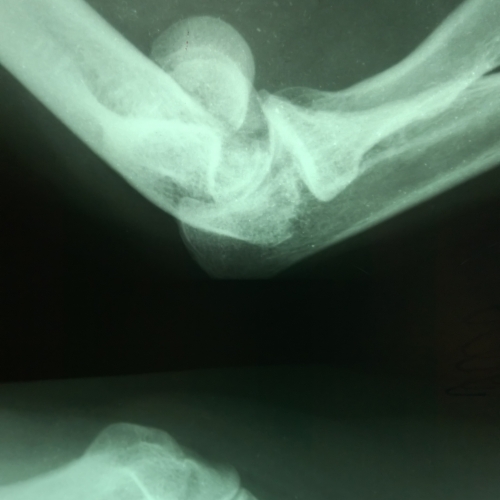

Закрытый перелом мыщелка плечевой кости